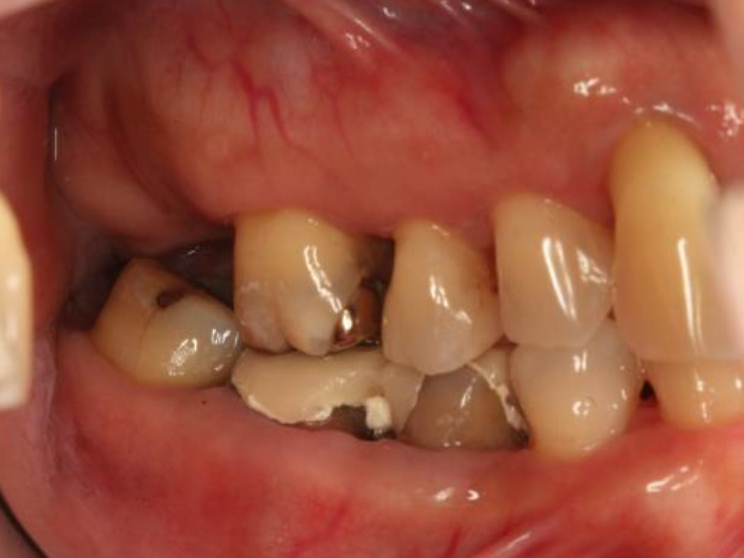

歯周基本治療・根管治療・歯周外科処置を行なった症例

初診時

歯周基本治療・

根管治療後

歯周外科処置

歯周外科処置後

初診時年齢:

治療:歯周病治療・う蝕治療

治療法:歯周基本治療、歯周外科治療、感染根管治療

治療期間:1年3ヶ月

費用:保険診療

リスク・副作用:歯周外科処置後に出血、腫れ、あざが出ることがありますが時間とともに治ります。術後3週間程度噛んだときの痛みや歯が浮いた感じがすることがあります。

感染根管処置中に腫れ、痛みが出ることがありますが時間とともに治ります。